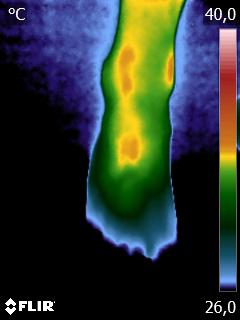

Como no caso do termograma abaixo de uma paciente do sexo feminino, 48 anos, sem comorbidades e que sofreu uma entorse de tornozelo há mais de uma semana e, mesmo tendo passado pela emergência com exame de Raio X, não foi atestado lesões graves e nem fraturas. Foi realizado uma Análise Termofuncional e detectado alterações térmicas condizentes com o relato de dor.

Estas informações foram suficientes para solicitação de exame de imagem (ressonância magnética) que atestou microfratura e outras lesões decorrentes do trauma.